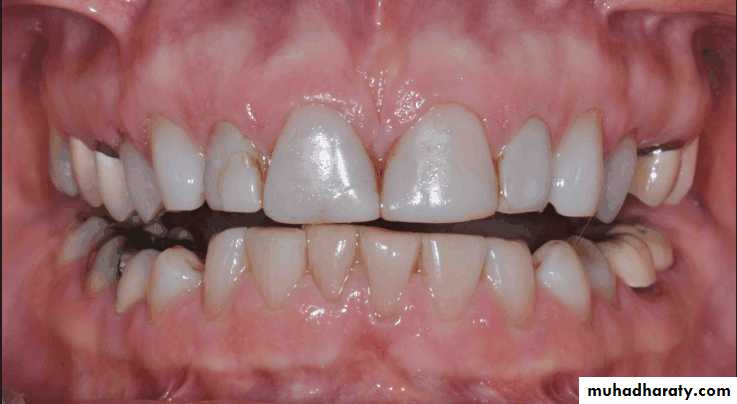

Traumatic vertical overlap

Clinical symptoms of traumatic vertical overlap

AbrasionMobility

Migration of the teeth

Inflammation , ulceration of the gingiva and palatal mucosa

Early recognition of problems and treatment with orthodontic or combined orthodontic and orthognathic surgical procedures are the treatment of choice